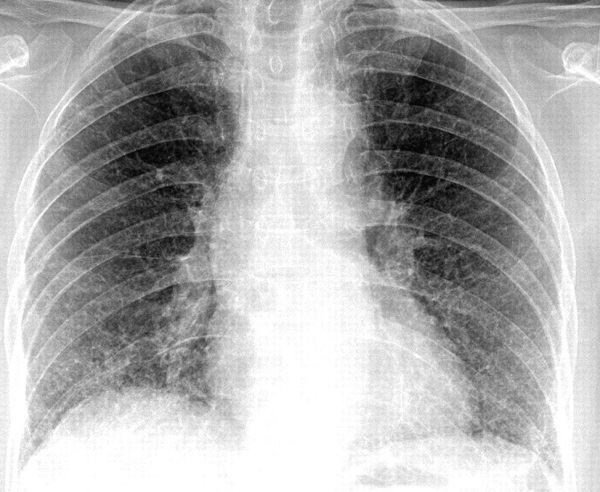

Ảnh minh hoạ: Internet